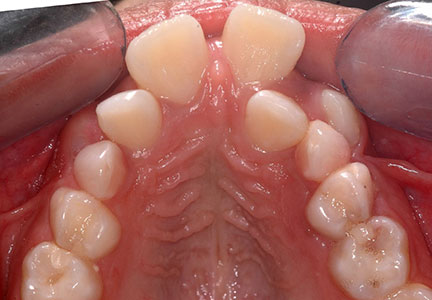

Normal wide arches

Narrow arches

Narrow arches – no room for the tongue here